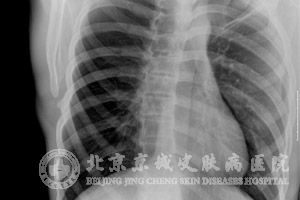

心脏脂肪瘤的发病没有性别的差异化,并且患者的年龄范围也基本没有限制,根据肿瘤的大小及其所处的部位会出现不同的症状表现。

如果是较小的肿瘤一般病人不会有什么症状表现出来,通常只会在体检或者时间时才能够发现;而如果是体积较大的肿瘤则会对心脏造成压迫,使得患者出现运动耐力下降,用力后明显感到气短,甚至可导致左心功能的损伤。在对患者进行查体时会发现其心音减弱,没有心脏杂音或者会出现二期收缩杂音。

房间隔脂肪瘤的体积太大就可能引起静脉回流受阻;心包脂肪瘤则会是心脏受到压迫并出现相应症状;还有病例出现过有腔内脂肪瘤而引发全身性的发热、血沉加快,甚至是导致周围的动脉栓塞;较大的心包下脂肪瘤可能对冠状动脉产生压迫导致心绞痛或者使心功能受干扰;心机内的脂肪瘤则可能是心脏的传到功能受干扰出西安心律失常的症状。